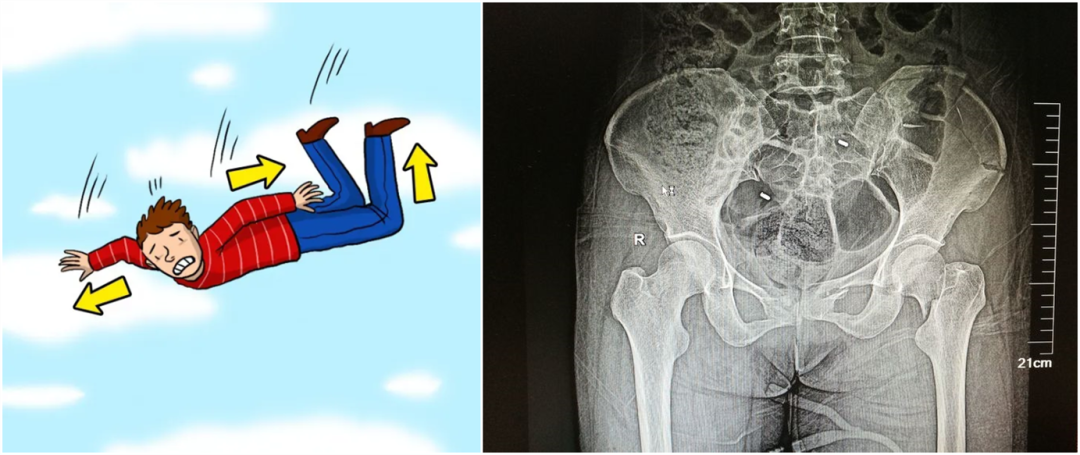

【醫(yī)療科普】:外傷性骨折影像

外傷性骨折

從暴力的大小來(lái)看,還可以細(xì)分為高能量的損傷和低能量的損傷。比如說(shuō),如果是車(chē)子撞的,從高處墜落,通常會(huì)造成高能量的損傷,而普通的跌倒造成的骨折,一般不太嚴(yán)重,可以說(shuō)是低能量的損傷。